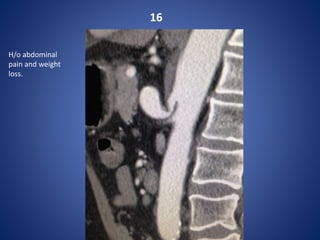

16

H/o abdominal

pain and weight

loss.

Coeliac artery compression syndrome

Or Median arcuate ligament syndrome

Compression of celiac axis with post-stenotic dilation. This case demonstrates classic fish

hook sign.

The median arcuate ligament is normally

several millimeters to centimeters superior

to the origin of the celiac artery.

In MALS, the ligament is anterior, rather

than superior, to the celiac artery, resulting

in compression of the vessel and a

characteristic hook-shaped contour.